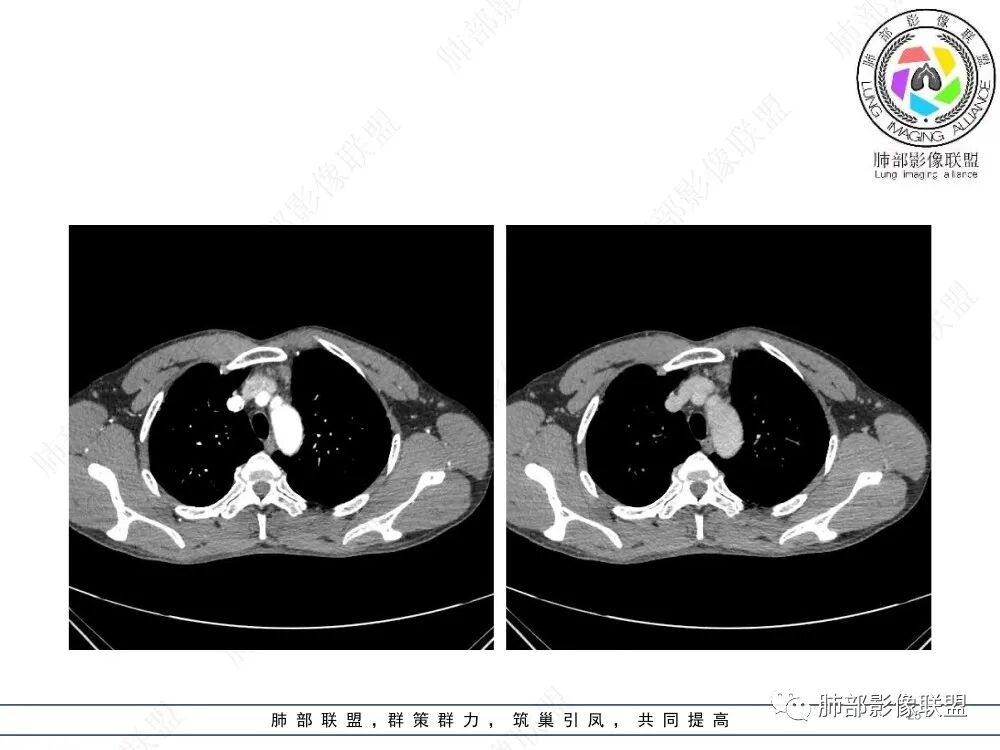

流心明智:男,47,咳嗽、咳痰1年余。胸部CT:前纵膈偏左类圆形肿块,瘤肺界面清晰光整,纵隔侧部分层面絮状影?平扫密度较均匀,增强后轻度强化,内可见宽带及线样低密度分隔。邻近左上肺受压凹陷。考虑胸腺肿瘤,AB型?胸腺Ca?鉴别淋巴瘤、N源性肿瘤、CD等。

南边:支持前纵隔、胸腺瘤首选,晨读其实定位上还是有点难度,定性常规还是考虑胸腺瘤,其他的几率比较低一些,需要鉴别的是胸膜SFT,神经源性,可惜的是没重建,一直在犹豫胸膜来源的可能性。

2、影像特点:前纵隔偏左侧软组织影,密度相对均匀,未见明显包膜钙化及实质内钙化,局部边缘浅分叶,周围脂肪间隙密度增高、浑浊,未见侵犯大血管、未见纵隔内淋巴结转移、未见侵犯心包内结构、未见胸膜转移结节、未见肿块沿着纵隔胸膜蔓延,未见胸腔积液。增强后动脉期不均匀强化,未见明显纤维分隔。

3、 病 例 小 结:40岁以上,前纵隔偏侧性生长的肿块,常规考虑胸腺瘤。难点就在于胸腺瘤的分型。但是对于前纵隔占位影像诊断的关键在于区分胸腺囊肿、胸腺瘤、胸腺癌及其他恶性肿瘤。至于胸腺瘤,主要在于判断有无侵袭性。